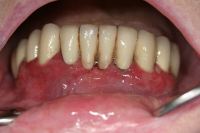

Ödematös, rodnad och blödande gingiva.

Förekomst av gingivala hyperplasier med djupa tandköttsfickor och svåra hygienförhållanden som följd.

Gingival hälsa på intakt och reducerat parodontium.

Parodontal stabilitet karakteriseras av framgångsrik behandling genom kontroll av lokala och systemiska riskfaktorer, vilket resulterat i

- minimal blödning vid sondering (BVS < 10 % av tandytorna)

- fickdjup < 3 mm